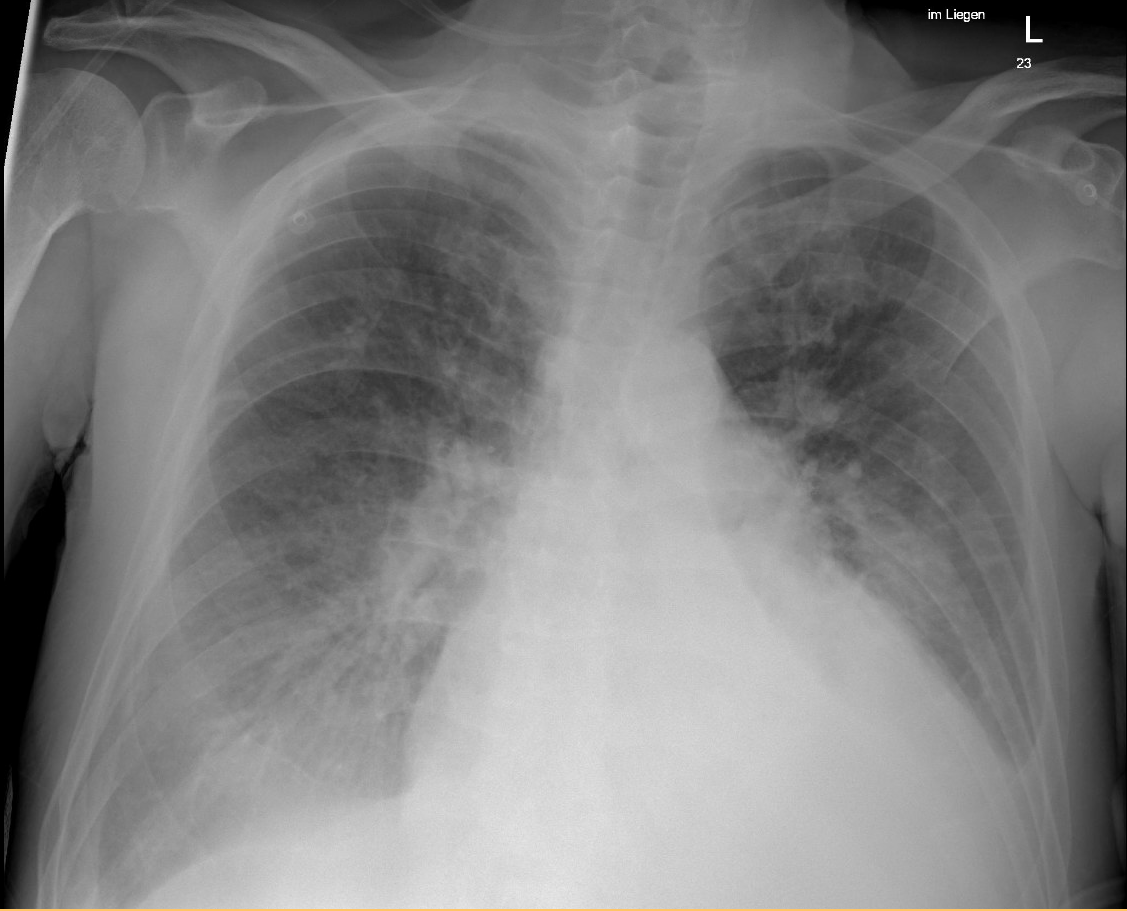

On admission, he showed fever (39.5 °C), hypoxia, and elevated inflammatory and cardiac markers (CRP 44 mg/l, troponin 733 ng/l, NT-proBNP 1586 ng/l – laboratory test results shown in Table 1). Chest X-ray (Fig. 1) revealed cardiopulmonary overload. Echocardiography demonstrated heart failure with mildly reduced ejection fraction (LVEF 43%) and a circular pericardial effusion.

Figure 1.